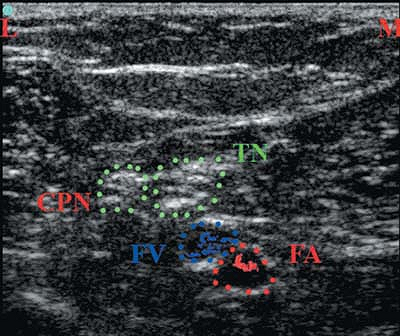

![]() |

|

Figure 43-14.

Visualization of the sciatic nerve terminal branches (common peroneal and tibial nerve) at the popliteal fossa level. TN, tibial nerve; CPN, common peroneal nerve; FV, femoral vein; FA, femoral artery; M, medial side of the patient; L, lateral side of the patient. |